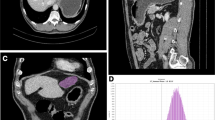

Machine learning algorithms

LASSO was performed to reduce the dimensionality of the features and to select optimal variables in the primary cohort (Fig. 5). Finally, MCHC, morphological type, Δmean D–N, histogram width in arterial phase, Entropy gray-level cooccurrence matrix (GLCM) 10 in portal phase, and mode, 90th percentile in delayed phase were integrated to build a multivariate model using the SVM algorithm in the primary cohort, which achieved an AUC of 0.879. The developed model was also applied to the validation cohort with an AUC of 0.921.

Feature selection was performed using the least absolute shrinkage and selection operator (LASSO) regression model. (a) Tuning parameter (λ) selection in the LASSO model used fivefold cross-validation via minimum criteria. Vertical lines were drawn at the optimal values using the minimum criteria and 1 standard error of the minimum criteria. The optimal λ value of 0.0356 with log (λ) = − 3.3359 was chosen. (b) LASSO coefficient profiles of the 27 selected features. A coefficient profile plot was generated versus the selected log (λ) value using fivefold cross-validation; seven selected features with nonzero coefficients were retained.